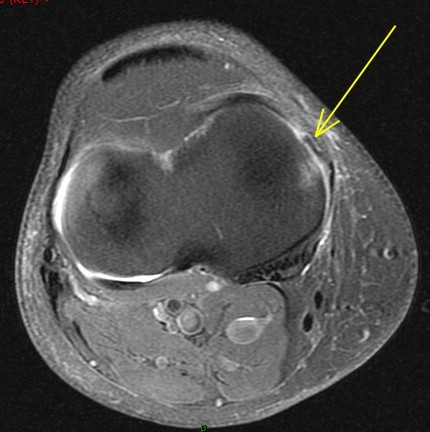

Figure 4 for case Unstable flap tear medial meniscus

Figure 4

With a displaced flap into the coronary recess. No sign of patellar dislocation. PD fat sat shows the inflammatory change that often accompanies and unstable tear. Displacement of meniscal tissue=instability.

Unstable flap tear medial meniscus